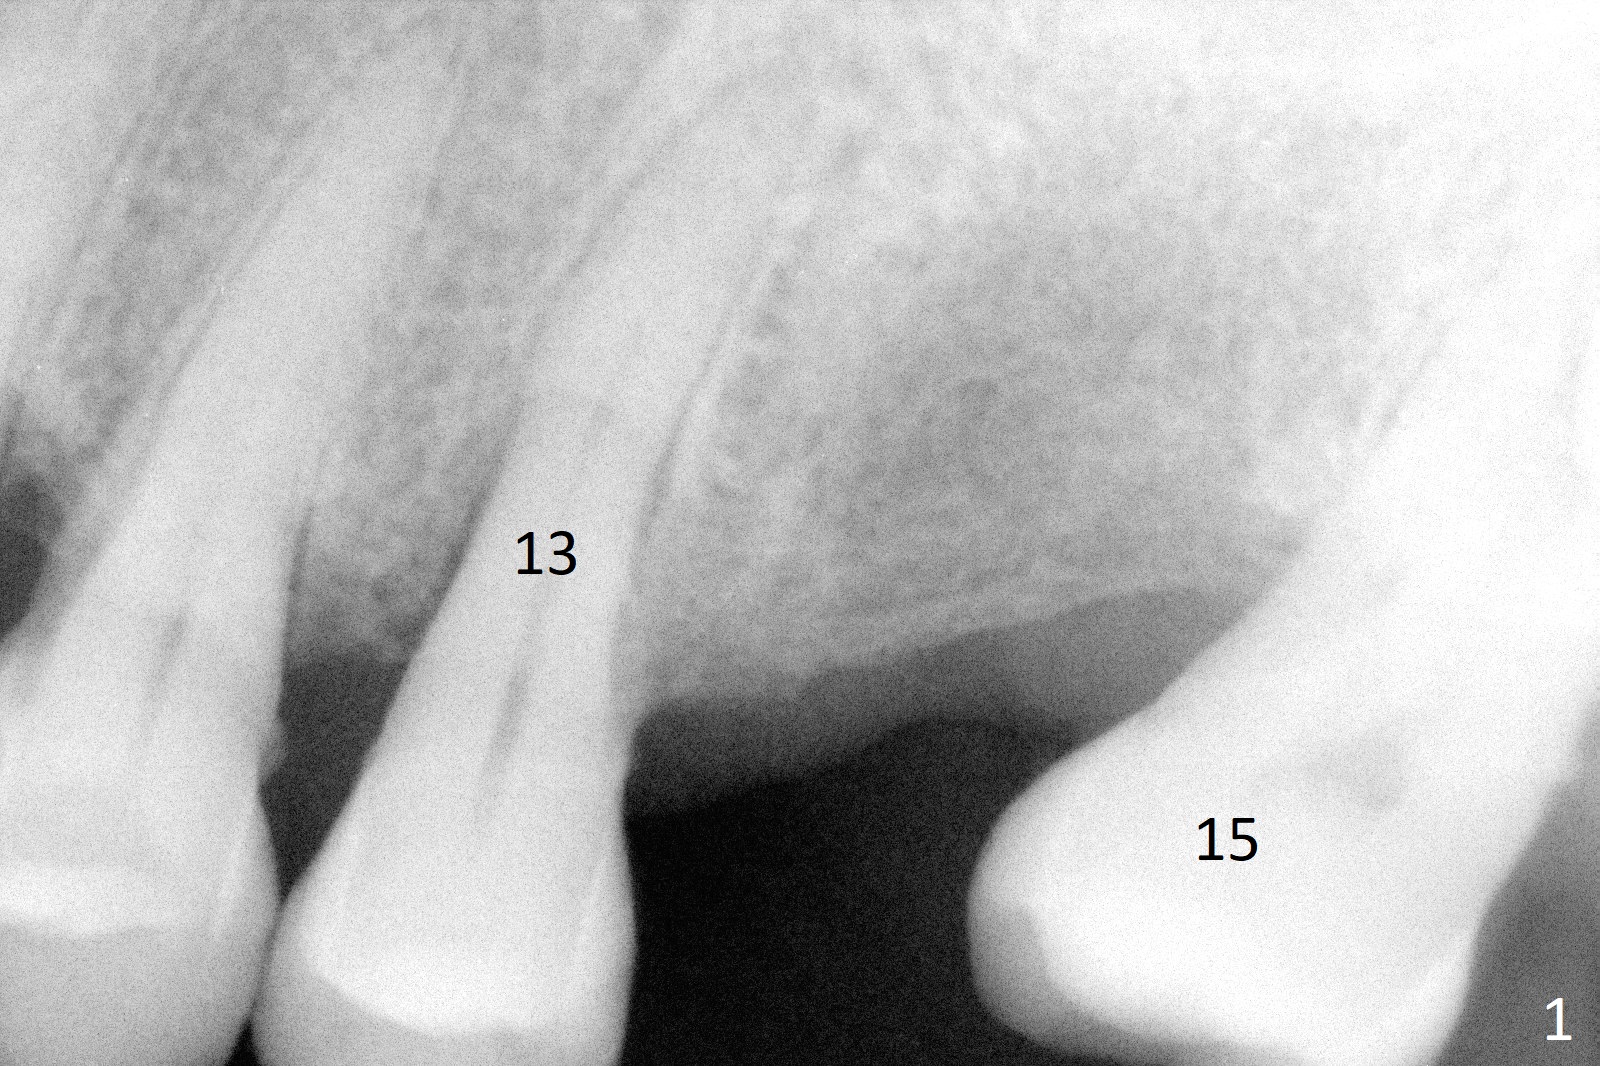

A 50-year-old man, a smoker, presents to clinic with pain of the tooth #15 with apparently occlusal trauma (Fig.1). Two years and three months after #15 extraction, he returns for #31 extraction (Fig.2) and socket preservation (Fig.3). The socket depth is 17 mm along the long axis of the socket 2.5 months post extraction (Fig.4, gingival level). Initial osteotomy is created in the mesial slope of the socket for 14 mm (Fig.5). After sequential osteotomy, a 6x17 mm tap is seated shallower (Fig.6) than the 2 mm drill (Fig.5). Following further osteotomy, a 7x14 mm implant is seated incompletely (Fig.7), which was not found intraop. The implant becomes loose with purulent discharge 19 days postop. The patient returns for 2nd placement 2 months post implant removal (Fig.8). Osteotomy is created probably in the mesial slope with 17 mm (bone level, Fig.9). After insertion of 5 (Fig.10) and 6 (Fig.11) x20 mm taps (tissue level), a 6x20 mm tissue-level implant is placed with clearance from the Inferior Alveolar Canal (Fig.12 yellow dashed line). The implant is restored 8.5 months postop (Fig.13) without bonding 5 mm 0 degree unipost. The crown dislodges 4 months post permanent cementation. Still the patient complains of small crown without occlusal contact. Impression is taken for a new normal-sized crown. The new crown becomes loose 1 year 9 months post cementation (Fig.14). The teeth #14 and 15 remain unrestored.